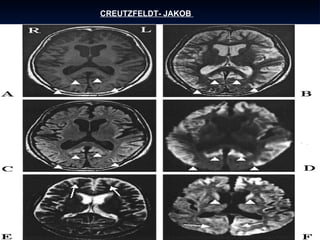

CREUTZFELDT-JAKOB La enfermedad de Creutzfeldt-Jakob  es un mal neurológico con formas genéticas hereditarias y también contagiosas, producidas por una proteína llamada prión (PrP). Si bien los casos hereditarios e infecciosos están perfectamente documentados, la causa de la aparición del prión es desconocida en la mayor parte de los casos informados. Se trata de una enfermedad de naturaleza degenerativa y pronóstico mortal que afecta aproximadamente a una persona por millón (prevalencia de 1:106) a nivel global. En Estados Unidos hay 127 pacientes de ECJ y sus variantes (2006). De acuerdo con la evidencia disponible, la ECJ resulta del plegamiento anormal de un prión. Este fenómeno parece estimular a que otras proteínas alteren sus formas, afectando su capacidad para funcionar. Por esto, se la clasifica entre las enfermedades priónicas o encefalopatías espongiformes transmisibles (EET), caracterizadas por presentar una forma anómala de la proteína priónica celular (PrPC). Estas enfermedades pueden existir en formas esporádicas (idiopáticas), hereditarias, y adquiridas. El término espongiforme alude al aspecto esponjoso que presenta en la autopsia el cerebro afectado.

CREUTZFELDT-JAKOB La enfermedadde Creutzfeldt-Jakob es un mal neurológico con formas genéticas hereditarias y también contagiosas, producidas por una proteína llamada prión (PrP). Si bien los casos hereditarios e infecciosos están perfectamente documentados, la causa de la aparición del prión es desconocida en la mayor parte de los casos informados. Se trata de una enfermedad de naturaleza degenerativa y pronóstico mortal que afecta aproximadamente a una persona por millón (prevalencia de 1:106) a nivel global. En Estados Unidos hay 127 pacientes de ECJ y sus variantes (2006). De acuerdo con la evidencia disponible, la ECJ resulta del plegamiento anormal de un prión. Este fenómeno parece estimular a que otras proteínas alteren sus formas, afectando su capacidad para funcionar. Por esto, se la clasifica entre las enfermedades priónicas o encefalopatías espongiformes transmisibles (EET), caracterizadas por presentar una forma anómala de la proteína priónica celular (PrPC). Estas enfermedades pueden existir en formas esporádicas (idiopáticas), hereditarias, y adquiridas. El término espongiforme alude al aspecto esponjoso que presenta en la autopsia el cerebro afectado.